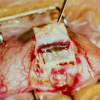

Methods: Non-randomised prospective trial involving consecutive patients. 100 eyes of 100 patients with medically uncontrolled primary and secondary open angle glaucoma. A superficial scleral flap was raised and a deep sclerectomy was performed in the scleral bed. Schlemm's canal was opened and dissection of the cornea was performed up to Descemet's membrane, at which point aqueous percolated through the remaining trabeculo-Descemet's membrane. A collagen implant was sutured radially in the scleral bed. Visual acuity, intraocular pressure (IOP) measurements, and slit lamp examinations were performed before surgery and after surgery at 1 and 7 days, and 1, 3, 6, 9, 12, 18, 24, 30, and 36 months.